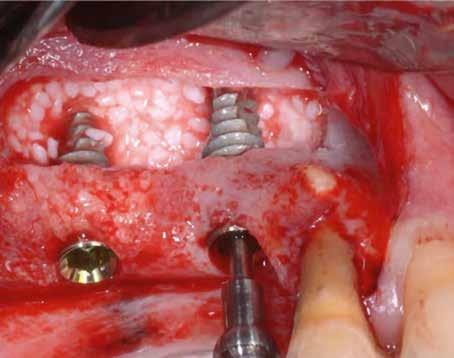

1. 3. 5. 8. 2. 4. 6. 7.

60/40 arányú keverésével történt (5–7. ábra), A-PRF és A-PRF/S-PRF membránokat készítettünk (8. ábra). Az alveólusokat a grafttal feltöltöttük, a felső front régióban vertikális augmentációt végeztünk a tervezett alveoláris csontmagasság elérésének céljából (9–10. ábra). A vertikális augmentáció támogatására titán mikrocsavarokkal rögzített, titánerősítésű teflonmembránokat alkalmaztunk, amelyekre egy rétegben A-PRF membránokat, és egy rétegben A-PRF/S-PRF membránokat helyeztünk. Az alsó állcsont esetében vertikális augmentáció nem volt szükséges, célunk az alveoláris kemény- és lágyszöveti struktúrák prezervációja volt, a graftot csak PRF memb-

9. 11. 13. 16. 10. 12. 14. 17. 15.